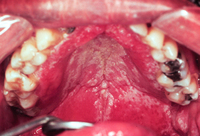

Candidíase oral

Candidíase pseudomembranosa no diabetes

Do acervo de Fariba Younai, UCLA School of Dentistry, Los Angeles